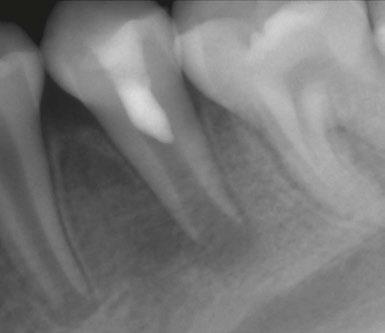

Figure 3 (left): Preoperative CBCT scan of tooth No. 20 showing evidence of a wide open apex. Figure 4 (right): Bleeding noted in the canal immediately after removing the GentleWave platform

Figure 1 (left): Dens evaginatus noted on the occlusal surface. Figure 2 (right): Preoperative periapical radiograph of tooth No. 20 showing evidence of apical periodontitis and a wide open apex

diagnosis of a necrotic pulp and symptomatic apical periodontitis of tooth No. 20 (Figures 2 and 3).